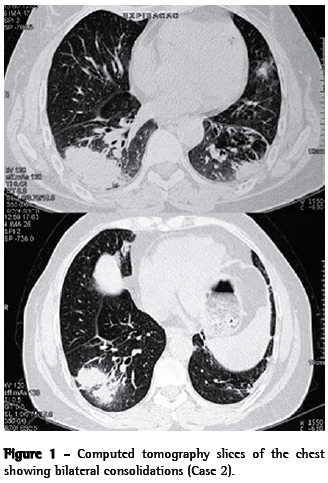

A 58-year-old female nonsmoker reported cough, moderate weight loss, fatigue and joint pain. The patient had a history of childhood asthma. After age 40, she experienced recurrence of the asthma-a fact that she attributed to contact with paints and solvents in the workplace. The patient used inhaled formoterol and budesonide (12/400 µg) daily, achieving satisfactory symptom control. A chest X-ray and a tomography scan of the chest showed bilateral consolidations and bronchiectasis in the lower lobes (Figure 1). Laboratory tests revealed the following: hematocrit, 41,1%; hemoglobin, 13.7 g/dL; leukocytes, 8,970, with lymphopenia (1,076 lymphocytes); ANF, present (1:160), with a dotted nuclear pattern; ESR, 56 mm/h; and C-reactive protein, 27.60 mg/L. At the time, Wegener's granulomatosis was suspected due to antineutrophil cytoplasmic antibody (ANCA) serum positivity. There was no upper airway involvement.

Here, we have described two cases of KFD. The actual incidence of this disease is estimated to range from 0.5% to 5% of all cases of adenopathy analyzed histologically.(15) In a retrospective study of 1,724 lymph node biopsy samples, KFD was found in 36 cases.(16) Various infectious agents, such as Epstein-Barr virus, herpes virus 6, herpes virus 8, parvovirus B19, parainfluenza virus, Yersinia spp. and toxoplasma, have been proposed as antigenic stimuli.(1) In our report, both patients presented bilateral consolidations, consistent with an infectious or inflammatory process. Although no infectious germs were identified, it is possible that this was the antigenic stimulus for the development of KFD.